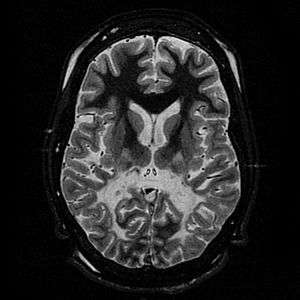

White matter, with reduced volume and increased signal intensity. The anterior white matter is spared. Features are consistent with X-linked adrenoleukodystrophy. | |

The Loes score is a rating of the severity of abnormalities in the brain found on MRI. It ranges from 0 to 34, based on a point system derived from the location and extent of disease and the presence of atrophy in the brain, either localized to specific points or generally throughout the brain. A Loes score of 0.5 or less is classified as normal, while a Loes score of 14 or greater is considered severe. It was developed by neuroradiologist Daniel J. Loes MD and is an important tool in assessing disease progression and the effectiveness of therapy.[12]